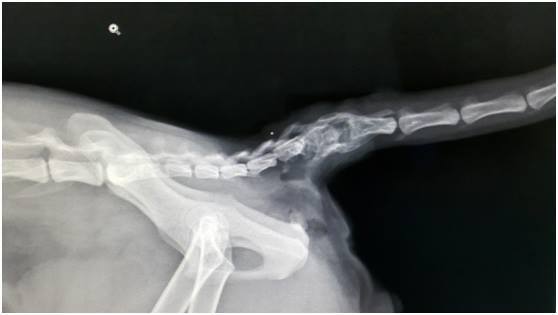

主題: 被惡犬咬傷的阿良 申請者姓名: 臺北市支持流浪貓絕育計劃協會 花色: 申請日期: 2015-11-27 17:44:51 申請者部落格: 申請者臉書網址: 所在縣市/合作醫院: 台北市/其他院所醫助專案(醫院請先MAIL溝通) 治療費用: 67900元 需求人數: 70人 已結案 (2023-01-18 23:38:05) 報名人員: 吳飽寶(已付款)、Frenkie Lee(已付款)、JobaMiday(已付款)、Chou Yun(已付款)、Olivia Huang x2(已付款)、Eeron Hsi(已付款)、Alisa Huang(已付款)、吳飽寶(已付款)、菲小比(已付款)、高小貓(已付款)、覺妙(已付款)、維尼(已付款)、Winnie Lu x2(已付款)、我愛摺耳貓(已付款)、skylung(已付款)、呂尚燁(已付款)、Ann Yang x2(已付款)、蘇洛克(已付款)、Gary Chen(已付款)、maysue(已付款)、Grace Liao x2(已付款)、Queenie Huang(已付款)、Ching-Ya Peng(已付款)、王可樂的日語教室(王頂倨) x2、vivian(已付款)、catannchen(已付款)、小花(已付款)、KC、KC(已付款)、bbfish1224(已付款)、Ariel Chen(已付款)、sandroio(已付款)、Ricky(已付款)、小黃(已付款)、Tzu-Pei Su(已付款)、燕子大人(已付款)、Ellen Lu(已付款)、Rosalind Tsai(已付款)、楊天賜(已付款)、Catty Chen(已付款)、Ray0322 x2(已付款)、心綸(已付款)、coolan(已付款)、Eric Chien(已付款)、楊慧君(已付款)、Chris Chen x5(已付款)、愛喵喵 x5(已付款)、Chuck Lin(已付款)、奶精(已付款)、yuan(已付款)、Paulala(已付款)、Yun Ting x6(已付款)、Tetsu x2(已付款)、 候補人員: 動物病情說明: 可愛的阿良被愛心志工發現時,

阿良在醫院檢查時,

除了尾根部皮膚缺損之外,

也檢驗出愛滋陽性、上呼吸道症狀,

9/19-28

院方先將阿良身上前醫院的縫線移除,

待其下方肉芽形成及減少傷口感染的狀況,

並將較小的右側傷口先試著以橫移皮膚的方式關閉,

另外也處理阿良的上呼吸道症狀。

10/9

阿良的右側皮膚缺損的小皮瓣因為張力過大所以壞死,

故將左右側缺損跟壞死部一起清創,

再使用右側後側乳腺皮膚皮瓣將缺損填補。

11/20

阿良在醫生的細心照顧下,

使得原本慘不忍睹的傷口一天一天漸漸地恢復、癒合。

在住院觀察兩個月之後,

醫生終於通知協會阿良已經恢復到可以接出院了,

但是阿良因為傷口傷的實在太嚴重,

假使皮膚癒合不佳的話,

則會需要進行尾巴截除,

以尾背部皮膚來關閉傷口。